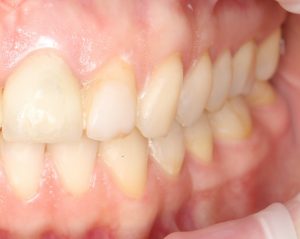

Но это еще не самое веселое. Допустим, мы решили проблему соединения «имплант-абатмент», у нас нет проблем с люфтами, а сам имплантат настолько хорошо интегрировался, что способен любую нагрузку в любом направлении. Возникает другая проблема — размер супраструктуры и соответствие ее нормальной биологической длине коронки зуба:

На фотографии выше, коронки опираются на обычные импланты, но даже в этом случае увеличение высоты супраструктуры усложняет гигиену и требует более пристального дальнейшего наблюдения. С ультракороткими имплантами, если честно, всё еще хуже.

Как будет выглядеть такая конструкция? Какой длины будут коронки? Возможно, на эстетику даже можно забить, ведь для некоторых людей красота зубов в боковом сегменте челюсти за пределами эстетически значимой зоны не так важна, но… как быть с уходом за протетической конструкцией и ежедневной гигиеной? Ведь, чем больше по размеру протез, тем сложнее за ним ухаживать. Тем больше мест, где может остаться зубной налет, а это, как вы понимаете, может привести к очень неприятным последствиям — периимплантиту, что для ультракоротких имплантов очень критично. А застревание пищи между протезом и десной? Можно ли назвать это «повышением качества жизни пациента»? Вряд ли.